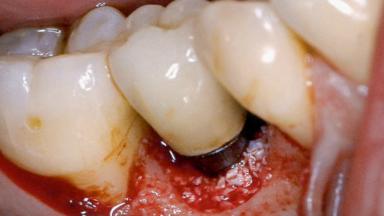

Peri-Implantitis Modified by the Presence of Submucosal Excess Cement: Reconstructive Therapy and a Ten-Year Follow-up

This case outlines the reconstructive therapy by Giovanni Salvi resulting in defect fill and inflammation-free peri-implant soft tissues at 10-year follow up. This case highlights the importance of regular monitoring of implants during supportive therapy.

A 30-year-old female patient was referred to the Department of Periodontology of the University of Bern, Switzerland, by a private dentist. Tooth 45 was congenitally missing and had been replaced with an implant three years prior to the first visit at the Department of Periodontology.